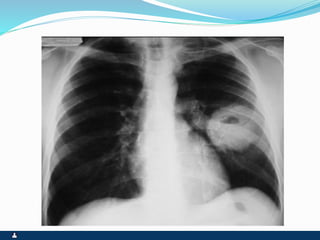

OPACIDADE

SINTOMAS SINAIS

 OLIGOSSINTOMÁTICOS

OU ESPECÍFICOS

 COMPRESSIVOS

 INVASIVOS

 COMPLICAÇÕES POR

RUPTURAS

 RETRAÇÕES OU

ABAULAMENTOS

 EXPANSIBILIDADE NORMAL

OU REDUZIDA

 FTV REDUZIDO OU AUSENTE

 MACICEZ

 MV REDUZIDO OU AUSENTE

 RONCOS E SIBILOS

EVENTUAIS

 ESTERTORES BRÔNQUICOS E

ALVEOLARES EVENTUAIS